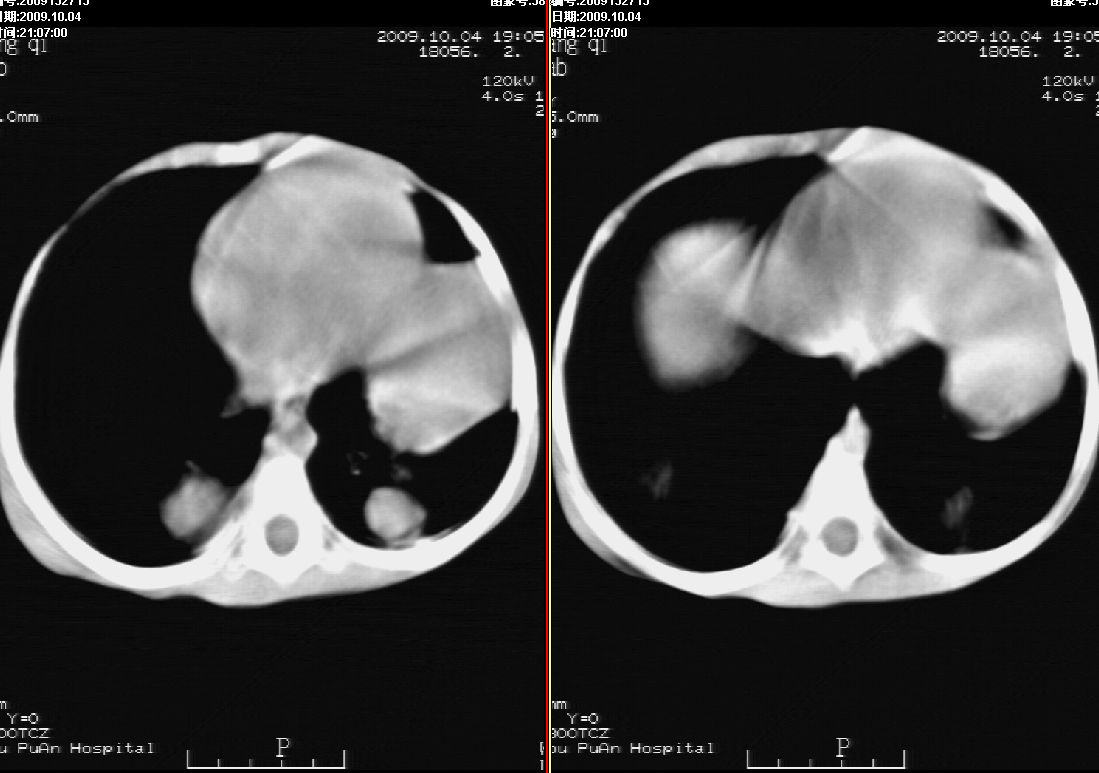

标题: PED2927:马某,男,两岁,发现血尿4天,请大家看看,发表 [打印本页]

标题: PED2927:马某,男,两岁,发现血尿4天,请大家看看,发表

右肾巨大囊性占位病变,其内密度不均,正常肾结构消失,肝脏,肾上腺及肠管等受压移位。双肺内多发大小不等的结节及块状影。考虑右肾母细胞瘤伴双肺多发转移。

肾母细胞瘤(wilms),系儿童最常见的恶性肿瘤,好发于3岁以下儿童,瘤体较大,主要由胚胎性肉瘤样细胞和上皮样细胞构成,临床以腹部肿块;血尿和高血压为主要体征。

ct表现:密度不均匀的大肿块存在;出血和坏死。与神母鉴别点:wilms易向颅脑转移,而神母易往肺转移。

ct表现:密度不均匀的大肿块存在;出血和坏死。与神母鉴别点:wilms易向肺转移。而神母易往颅脑转移.